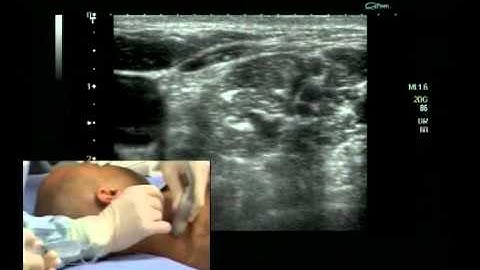

Interscalene Block (ultrasound guided - in plane)